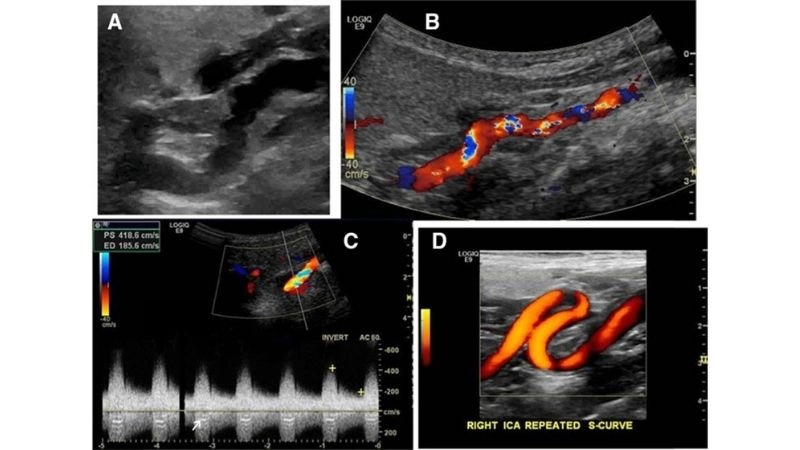

Images visual examples of Fibromuscular Dysplasia

Visual examples of Fibromuscular Dysplasia (FMD) typically highlight twisted arteries or a “string of beads” appearance in imaging scans.